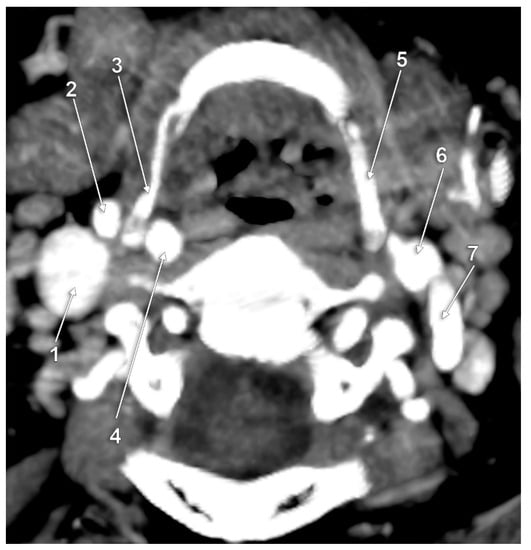

The Carotid–Hyoid Topography Is Variable

3. Results